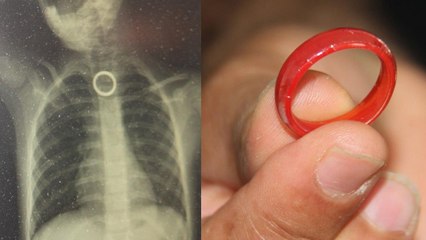

Yaya geçidinden geçen 5 yaşındaki çocuk ölümden döndü